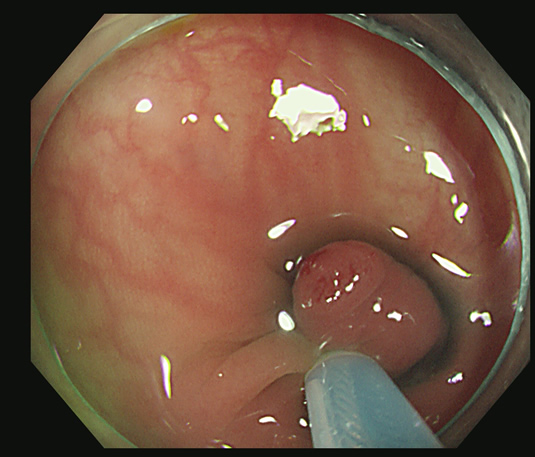

切除創に白い突起(CSDP)があり、よく見ると根本に粘膜の遺残が見られます

切除創を時間をかけて丁寧に観察することが重要です